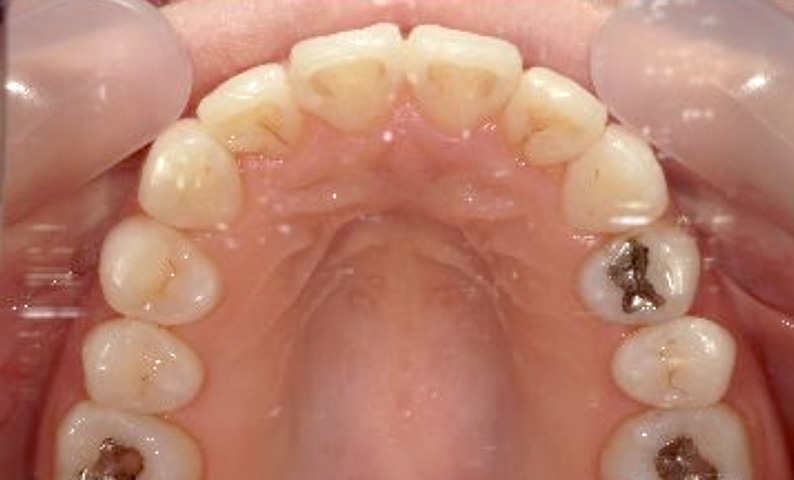

症例_024 上顎だけの部分矯正

治療期間:7ヶ月金額:30万円+税女性前歯のガタガタ上の前歯だけ

| Before | After |